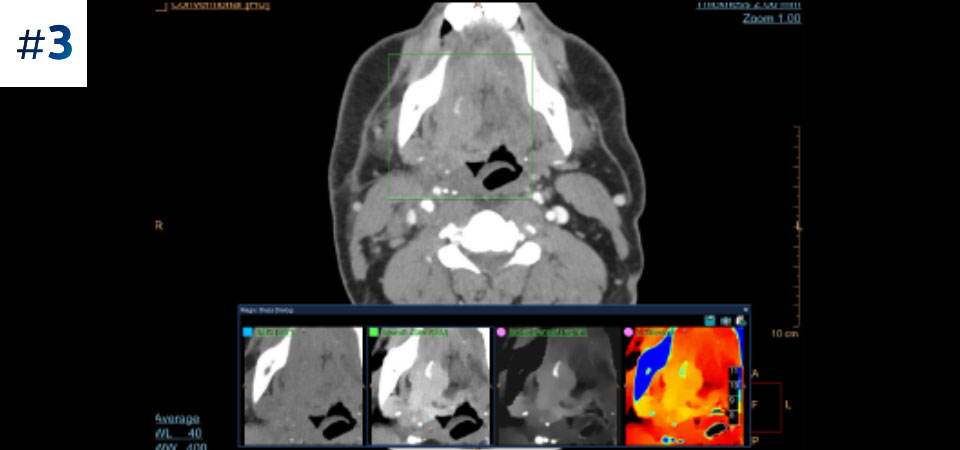

Guz szyi

Pobierz opisy przypadków tutaj

Opracowany przez firmę Philips tomograf komputerowy z detektorem spektralnym umożliwia akwizycję konwencjonalnych i spektralnych danych

w ramach jednego badania — bez konieczności zmiany stosowanych procedur pracy.